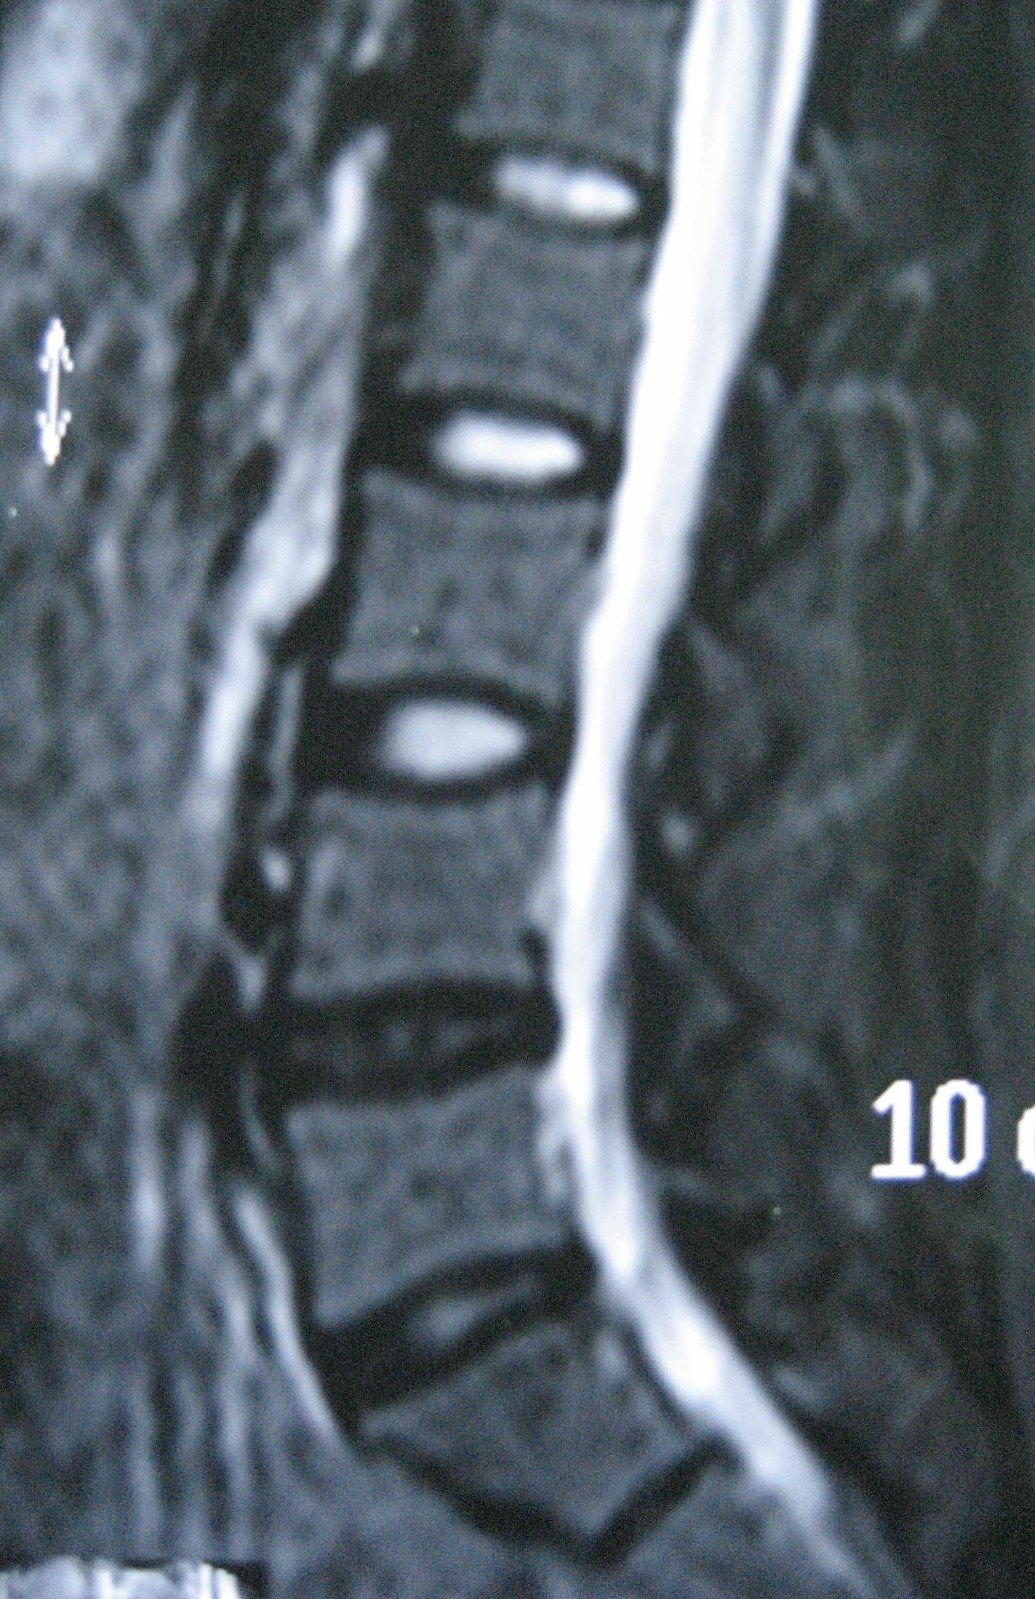

脊柱内镜辅助治疗脱垂游离型腰椎间盘突出1例

一例多发骶管囊肿合并腰椎间盘突出的手术治疗

腰椎后路复位椎间盘切除植骨融合内固定术治疗腰椎滑脱